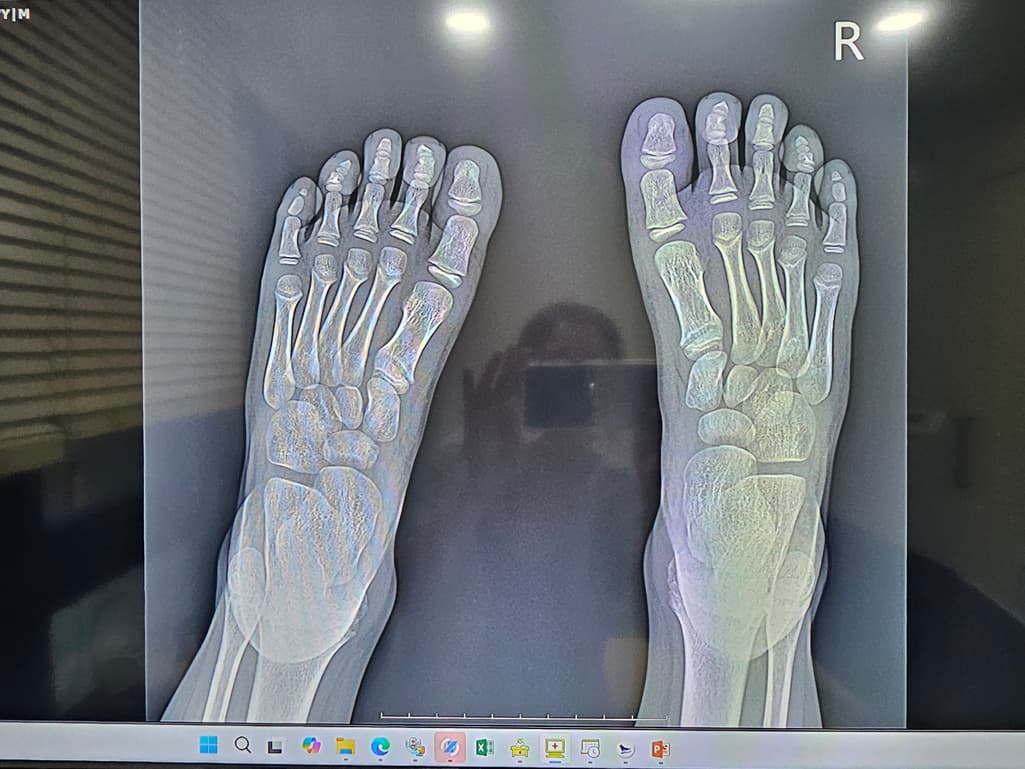

첫번째 사진은 엑스레이

두번째 세번째는 ct입니다

8세남아 맨바닥에서 축구하다가 땅을 찼어요ㅠ

수술하자하는데 제가 일주일만 경과보고프다해서 일단 통깁스만했는데ㅠ

핀 수술이 필요할까요?ㅠ